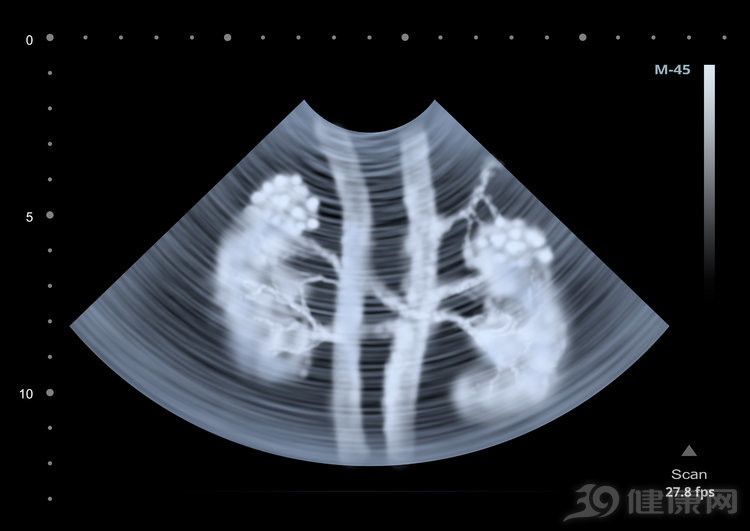

4、泌尿系统或者尿路感染

泌尿系统以及尿路感染也是导致尿毒素出现的常见因素之一,占据尿毒症诱因当中的百分之二十一,而尿路感染多数是因为细菌侵袭造成的,如果不及时治疗就会引起肾炎,长期下去就会伤害肾脏健康,导致尿毒症出现。